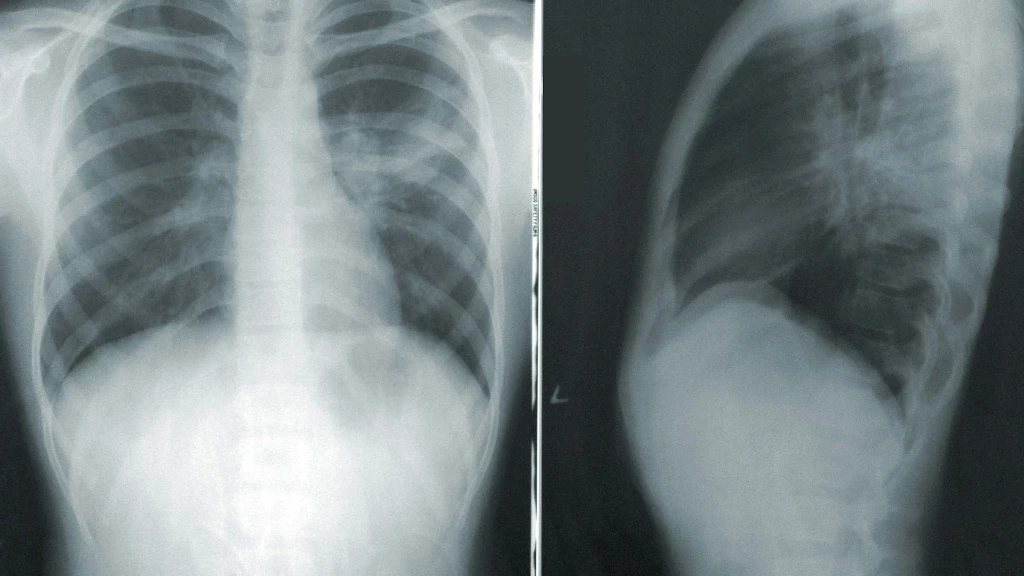

La tuberculosis respiratoria es una enfermedad infecciosa causada por la bacteria Mycobacterium tuberculosis. Su transmisión se produce por el aire, cuando una persona enferma de tuberculosis pulmonar tose, estornuda o escupe, liberando pequeñas gotas que contienen la bacteria. Esta característica facilita su propagación en entornos de cercanía y, en particular, en áreas con alta densidad poblacional, movilidad constante y condiciones de desigualdad social que pueden propiciar el hacinamiento. Aunque puede afectar a diversos órganos, la forma pulmonar o respiratoria es la más común y la principal vía de contagio.

Los síntomas de la tuberculosis respiratoria pueden ser insidiosos y a menudo se confunden con los de otras afecciones respiratorias comunes, lo que puede retrasar el diagnóstico y el inicio del tratamiento. Entre los signos de alerta se encuentran una tos persistente que puede ir acompañada de flema o incluso sangre, fiebre, una inexplicable pérdida de peso, fatiga generalizada y sudoración nocturna excesiva. Ante la presencia de una tos que persista por más de dos semanas, las autoridades sanitarias enfatizan la importancia de acudir a una unidad médica para una revisión oportuna.